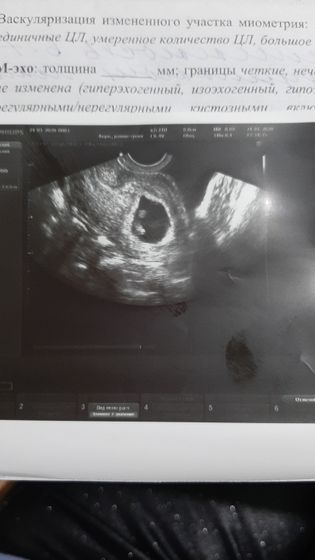

Эмбрион подрос 8.8мм, Пя 36мм.Жельочный мешок 6.2мм.амаот жёлтое тело было 18мм а стало 12мм.дюфастон пью по 3т… плодное яйцо стало круглое…